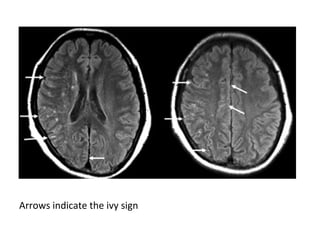

-The typical imaging findings of PRES are most

apparent as hyperintensity on FLAIR images in

the parieto-occipital and posterior frontal

cortical and subcortical white matter , less

commonly , the brainstem , basal ganglia and

cerebellum are involved

Patient with reversible neurological symptoms , the

abnormalities are seen both in the posterior circulation as

well as in the basal ganglia

Four days later most of the abnormalities have disappeared